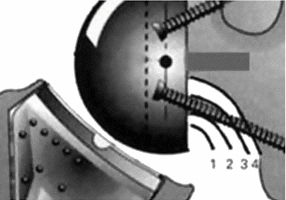

대신 반대로 상완골의 움직이면서 glenoid의 하방부를 notching 하는 부작용이 쉽게 생길 수 있습니다. 이를 scapular notching 이라고 합니다. base plate를 좀더 lateral inferior 하게 삽입하면 이를 예방할 수 있습니다. 또한 glenosphere 크기를 늘리고 lateral offset을 늘리는 방법도 있습니다.